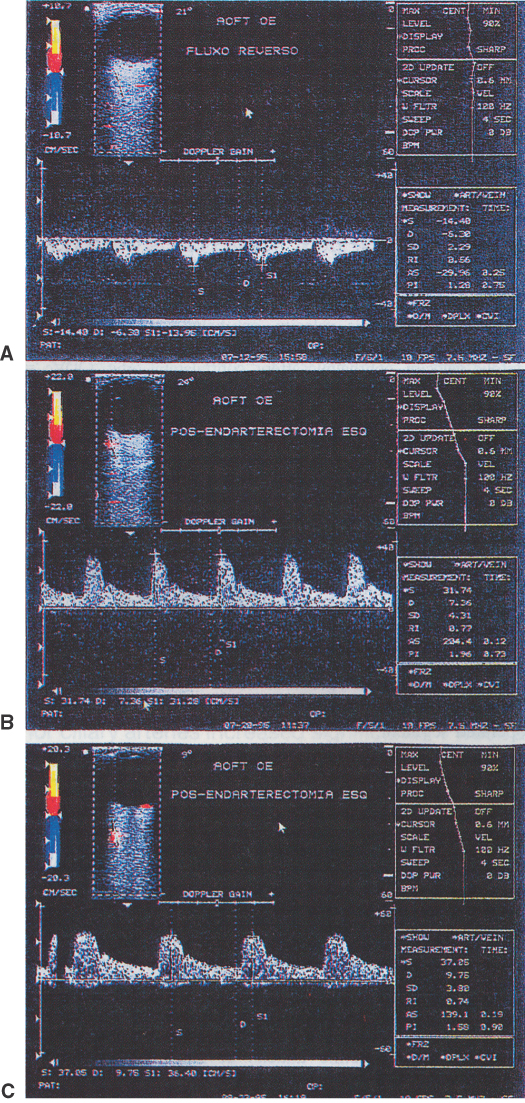

Clinically, it is possible to examine the blood flow velocity in the central retinal artery in a noninvasive manner, using a variety of techniques.21 The most useful appears to be color Doppler imaging, providing simultaneous Doppler and B-scan ultrasound images of the optic nerve head, which primarily represents flow in the central retinal artery.23 Studies using this technique demonstrate a marked reduction of or no blood flow in the central retinal artery with an acute central retinal artery occlusion that returns to normal with time.24